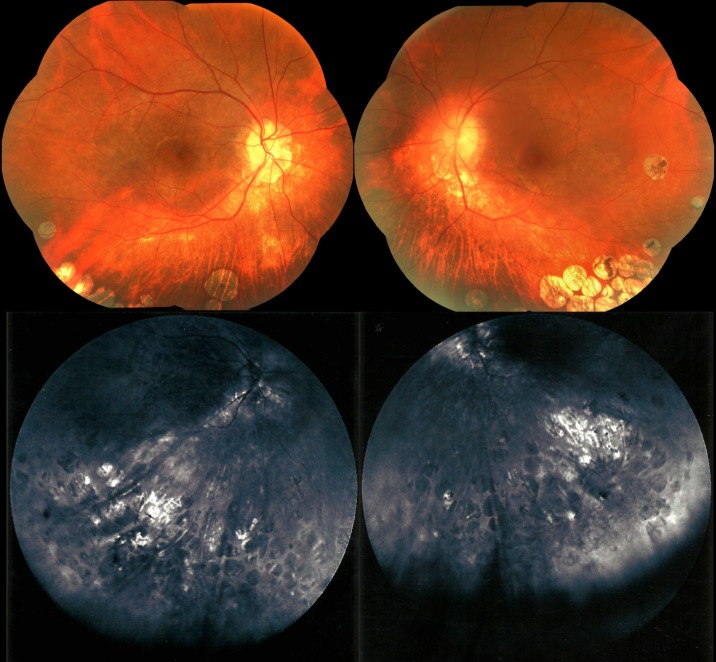

We present the case of a 39-year-old male with sectoral chorioretinal atrophy similar to that seen in gyrate atrophy (GA) but with a normal plasma ornithine level. Unlike previously reported cases of GA, he had below-normal plasma taurine concentration. Much remains unknown about the pathophysiologic mechanism underlying gyrate-like chorioretinal atrophy. The concomitant occurrence of GA-like phenotype and hypotaurinemia suggests a possible future avenue for research on this matter.